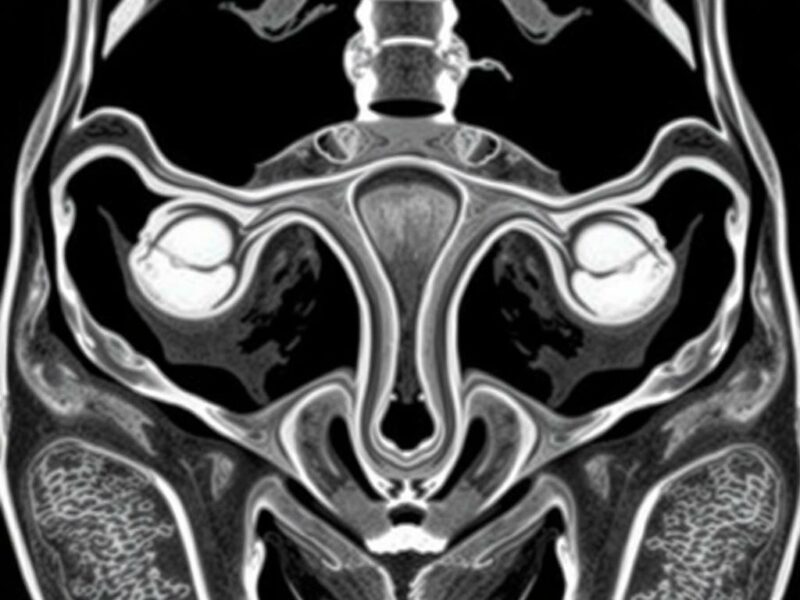

Técnicas de imagen para evaluar la vecindad entre útero, uréter, ovarios y trompas

La ecografía transvaginal es la primera herramienta: visualiza con detalle endometrio, miometrio, ovarios y colecciones anexiales; sin embargo, el uréter no siempre es visible salvo que esté dilatado. La resonancia magnética (RM) ofrece una visión multiplanar excelente para delinear adherencias, endometriosis profunda y relaciones entre masa y órganos. La tomografía computarizada (TC) es útil en urgencias y para ver órganos retroperitoneales y ureteres distendidos con contraste. La urografía intravenosa o la pielografía por TC pueden mapear la vía urinaria y su relación con procesos pélvicos.

En cirugía, la cistoscopia y la eco intraoperatoria o el sondeo ureteral pueden usarse para detectar o marcar el curso ureteral. La elección de la técnica depende de la pregunta clínica: ¿es la masa ovárica la que comprime al uréter? ¿Hay sospecha de fístula vesical? ¿Necesitamos planear una reconstrucción vascular o intestinal?